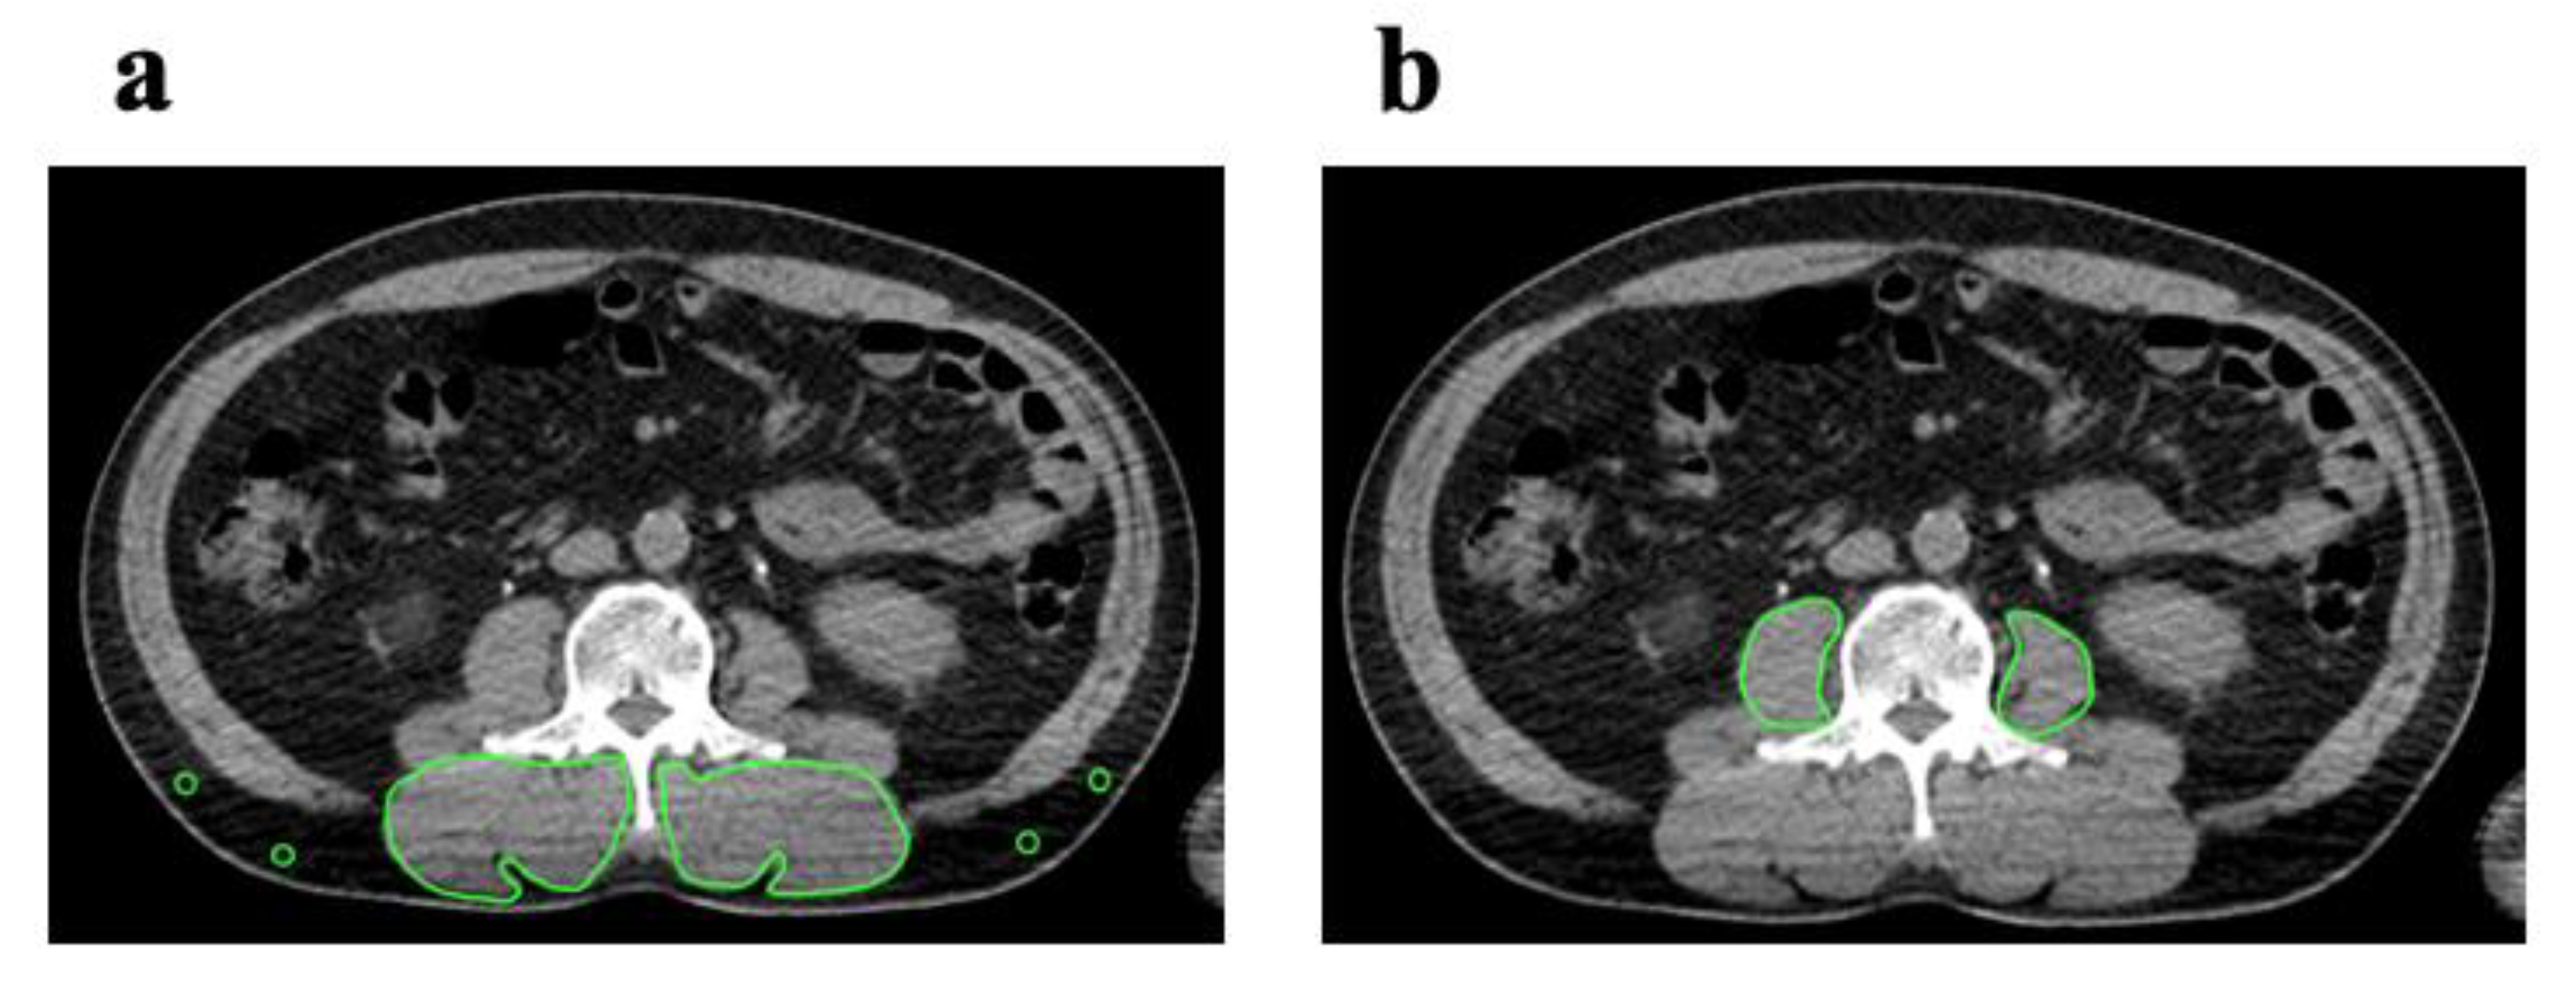

2.2. Image Analysis

2.3. Cut off Values of PMI and IMAC